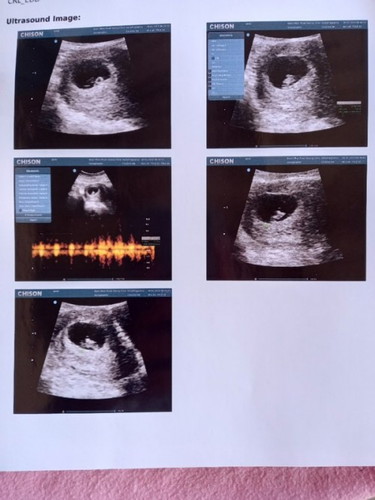

จากคนไข้ที่หมอบอกว่าไม่สามารถท้องเองได้โดยวิธีธรรมชาติ ซีสในรังไข่8เซนกับ5เซนบังท่อนำไข่2ข้างไข่ไม่สามารถตกเองได้ต้องผ่าตัดเอาซีสออกก่อนซึ่งก็มีความเสี่ยงที่อาจจะต้องตัดรังไข่ข้างใดข้างหนึ่งไปด้วย กลายเป็นเจ้าจิ๋วน้อย7w1d ในวันนี้พร้อมกับซีสของแม่ที่หายไปทั้ง2ข้างโดยไม่ต้องผ่าตัด ท้อง1ได้ลูกชาย ท้อง2-3 แท้ง ปัจจุบันท้องที่4ค่ะ🥰 #เป็นกำลังใจให้คุณแม่ๆที่เป็นผู้ป่วยมีบุตรยากทุกท่านขอให้สมหวังเช่นกันนะคะ💗